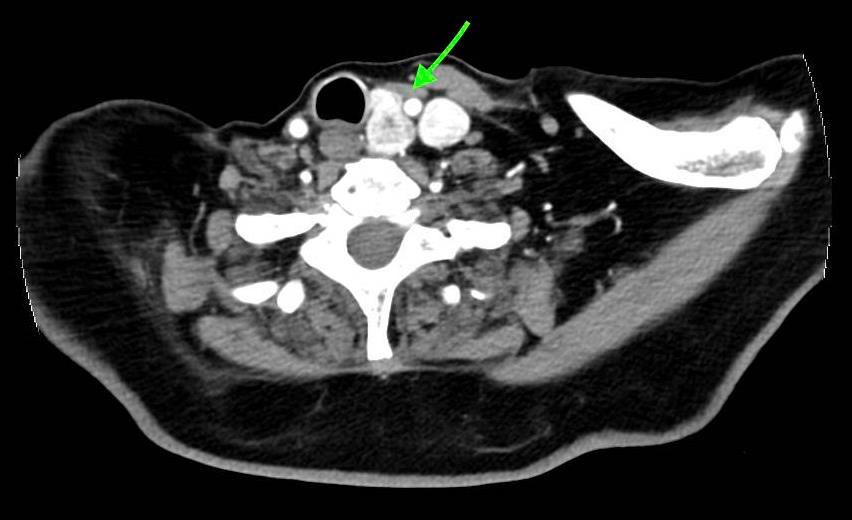

123 Unveiling the Rarity: Pleural Metastasis of Papillary Thyroid Cancer – A Case Report and Clinical Implications

Abigail Craig